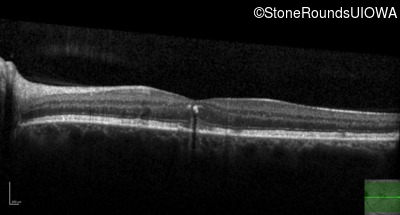

Age at visit: 49 years

This 49 year old man was first told he had a fundus abnormality on a routine eye exam at age 34. Ten years later he noticed some distortion just superior to fixation.

Age at visit: 49 years (Visit 2)

Pattern Dystrophy PRPH2 Gln239Stop CAG>TAG   AD